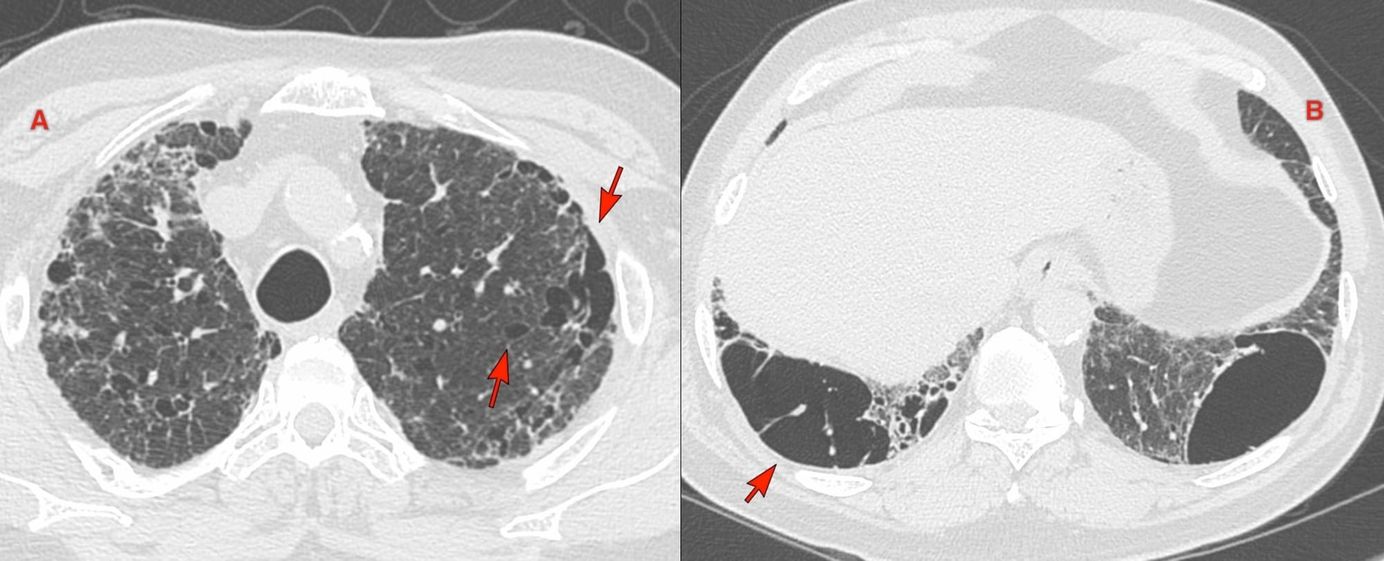

The PDIF sign is basically the presence of a fibrosing ILD typically compacted within the last 2 cm of the peridiaphragmatic lung and may suggest not just CTD-ILD but specifically myositis ILD